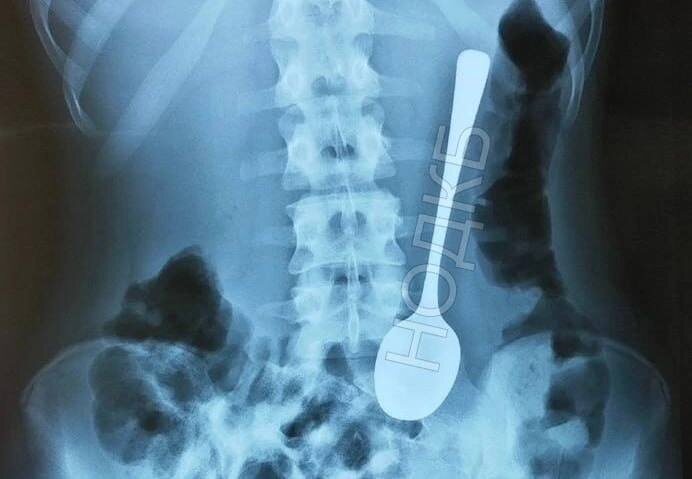

Нижегородский врач вытащил десертную ложку из ребёнка без наркоза Когда хирурги сообщили эндоскописту Александру Дворянинову, что в приёмном покое ребёнок с проглоченной чайной ложкой, он решил, что это розыгрыш. Но всё оказалось правдой. Врач с помощью гастроскопа достал ложку без наркоза и операций — аккуратно и профессионально. Даже опытные медсёстры были в шоке: такого за свою практику не встречали. Теперь эта ложка — экспонат в музее инородных тел НОДКБ.

Когда хирурги сообщили эндоскописту Александру Дворянинову, что в приёмном покое ребёнок с проглоченной чайной ложкой, он решил, что это розыгрыш. Но всё оказалось правдой.

Врач с помощью гастроскопа достал ложку без наркоза и операций — аккуратно и профессионально. Даже опытные медсёстры были в шоке: такого за свою практику не встречали.

Теперь эта ложка — экспонат в музее инородных тел НОДКБ.